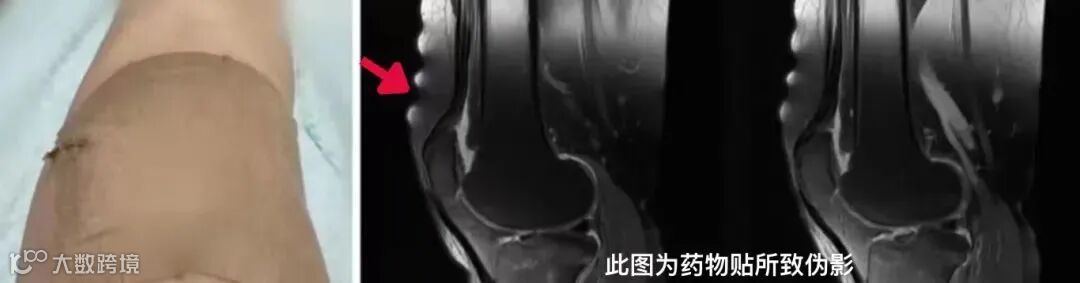

膏药

原料中含有金属成分的中医膏药、一些类似膏药的含有极少量金属成分的药物贴片,做磁共振检查也是要去除的。

一是因这些金属物质会引起磁场不均匀,产生伪影,对MR检查图像及诊断造成影响;

二是避免MR扫描时过热产生危险,尤其是贴片在发射RF线圈区域内,可导致少数患者诱发皮肤烧伤。